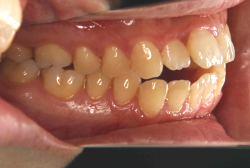

「出っ歯を治したい」という主訴で来院したケースです。診断の結果、「2級1類の上顎前突+軽度叢生」と判明しました。2級というのは、基本的に出っ歯の噛み合わせになっていることを言います。その中でも上の前歯が著しく外に反っているケースを、「1類」といいます。初診時の横向きの写真を見ると、それがはっきり分かります。上の前歯に押されて唇も膨らんで、審美線をかなりオーバーしています(審美線とは、鼻の先端と顎の先端を結ぶ線のことで、この線よりも唇は内側にある方が良いとされています)。

このような症状の場合は、前歯を内側に入れるためにかなり大量の隙間を必要とします。通常は上下左右の小臼歯を抜歯させていただくのが正解です。治療後は歯の角度が正しくなっただけでなく、唇の審美性が大幅に改善しました。もちろん噛み合わせ的にも正しい状態が確立しています。